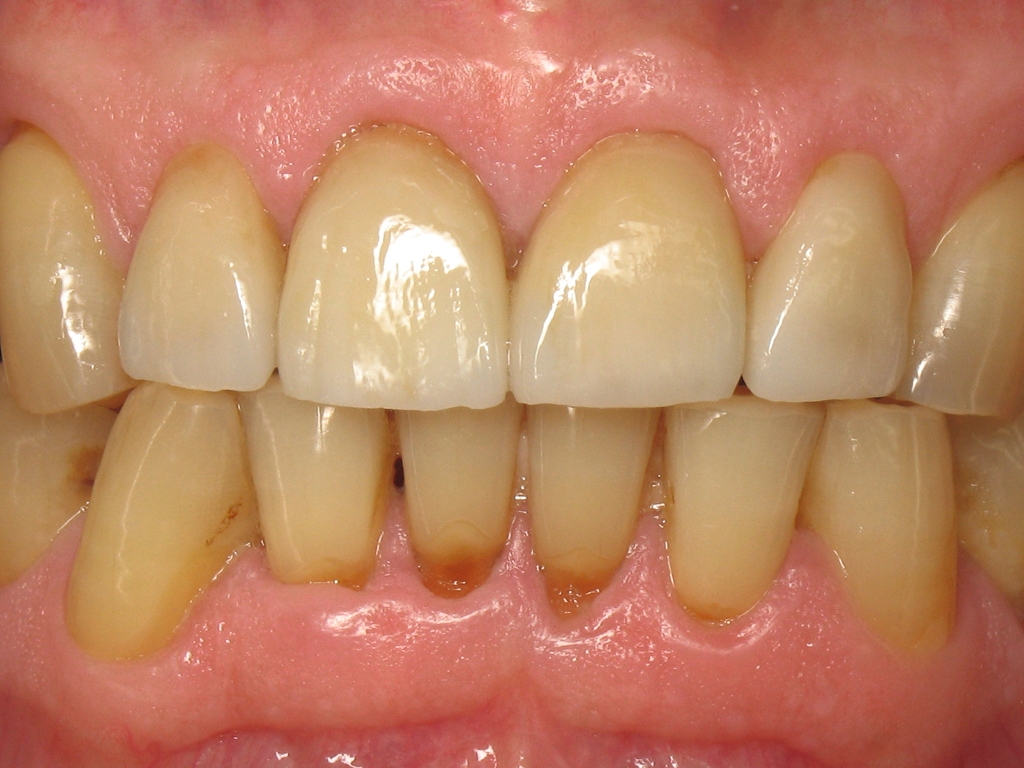

La figure 1 montre une situation clinique où le patient va pouvoir reprendre sa vie d’avant, avec le sourire au sens propre et au sens figuré. Les dents ont une forme, une position et une teinte harmonieuse, malgré des défauts mineurs, comme les lésions cervicales des incisives mandibulaires. La sante parodontale est également présenté avec l’absence de plaque ou d’inflammation gingivale. Ce que le lecteur est loin de se douter c’est que cette situation finale correspond à la pose de quatre couronnes sur les dents 12,11, 21 et 22.

Fig. 1: Situation finale.

Fig. 2 : Vue rapprochée de la situation finale.

La figure 2 nous montre en gros plan la qualité des restaurations et l’attention apportée par le prothésiste dentaire, dans la réalisation de ces couronnes. En effet, l’anatomie est harmonieuse et ne laisse aucun triangle noir au niveau des papilles gingivales. De plus, la teinte est naturelle avec une saturation progressive depuis le bord libre vers la région cervicale. Le technicien de laboratoire a ajouté une touche subtile de maquillant ocre en traits verticaux. Une attention toute particulière a été portée à ce cas clinique, pour un résultat qui dépasse les attentes du patient.